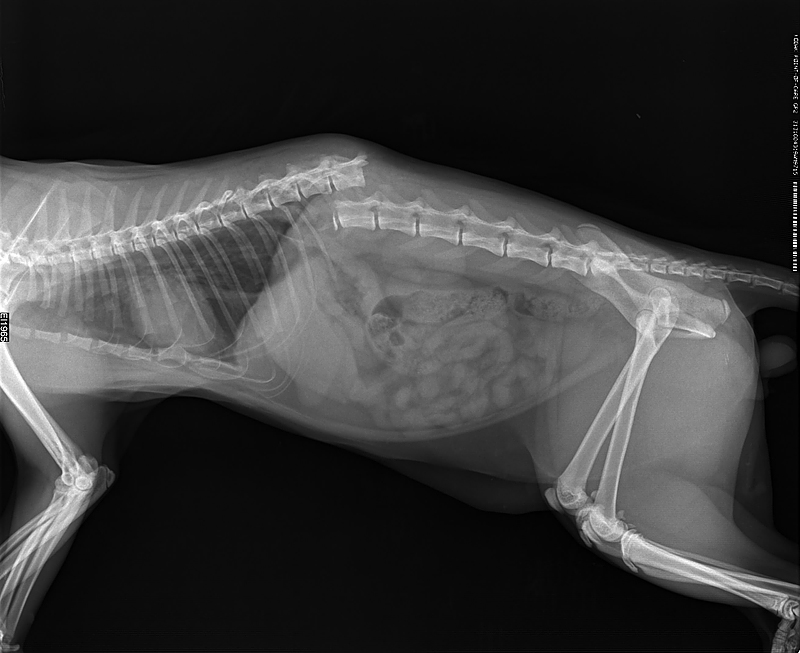

Заболевания позвоночника у домашних животных: диагностика и лечение

Раздел: Визуальные истории